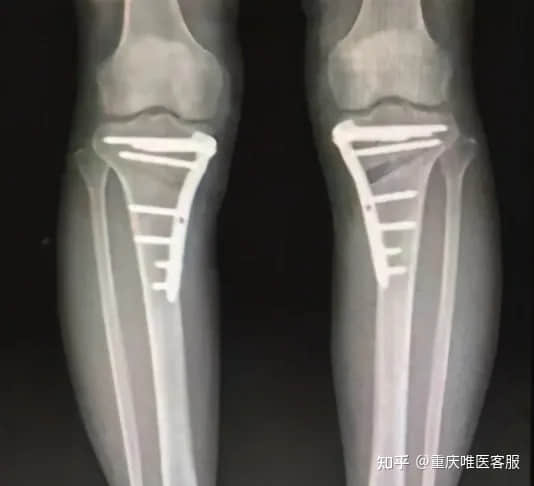

首先说说胫骨高位截骨手术。该术式最适合“罗圈腿”的病人,通过矫正膝关节负重力线,将膝关节着力点从内侧转移到中央或偏外位置,使内侧关节炎停止发展。截骨术完整保留了关节内的软骨、韧带和半月板,术后关节功能和本体感觉不受任何损失,特别受到活动需求较高的年轻患者的推崇。